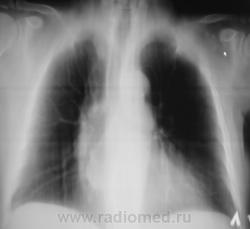

Пациент взят на контроль после флюорографии.

Произведено стандартное дообследование.

Рентгенограмма в прямой стандартной проекции.